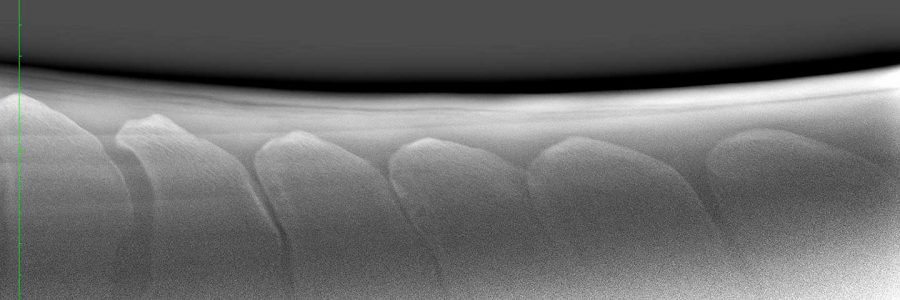

I en nyere, dansk undersøgelse har man forsøgt at afklare betydningen af røntgenstrålernes vinkel i forhold til vurdering af størrelse af mellemrummene mellem torntapperne i ryggen på heste. Altså: Giver røntgen et reelt billede af de tætsiddende torntappe?

Seks kadavere blev både røntgenundersøgt i op til otte forskellige vinkler og også CT-scannet.

Undersøgelsen viser, at det er vigtigt at røntgenstrålen er vinkelret på mellemrummene mellem torntapperne, men for mig at se er den væsentligste information i denne undersøgelse, at:

Røntgenundersøgelse konsekvent undervurderer størrelsen af mellemrummene i forhold til CT-scanning.

Det positive ved denne undersøgelse, set med mine øjne er, at vi, når vi vurderer røntgenoptagelser af ryggen i forbindelse med handelsundersøgelser, med større ro i sindet kan tillade os at “godkende” heste med tætsiddende torntappe. Røntgenbillederne “overdriver” nemlig tætheden af torntappene i forhold til det reelle mellemrum som en CT scanning viser af de tætsiddende torntappe.

Denne undersøgelse, og flere andre undersøgelser, dokumenterer den dårlige sammenhæng mellem røntgen-forandringer og de reelle kliniske rygproblemer, når der drejer sig om rutinemæssige undersøgelser af ryggen på heste.

Tager vi disse undersøgelser for gode varer, så åbner det op for at se på tætsiddende torntappe med mildere dyrlæge-øjne. Problemet er måske ikke så stort, som det ser ud på røntgen.